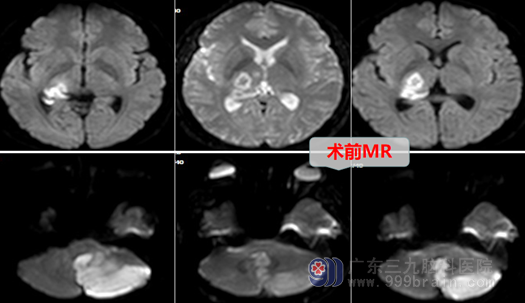

患者张某,35岁,在一天前骑行当中突发头痛,并伴有呕吐,且左肢乏力,胳膊抬不起来,说话也变得不利索,家人感觉不对,急忙拨打120急救电话。根据当地医院CT报告:左侧小脑半球大面积急性脑梗塞,为进一步治疗来我院就诊。

小脑半球大面积急性脑梗死可以导致后颅窝压力升高,容易引起枕骨大孔疝,导致死亡。故患者当日入院后,我科予以急诊行“后颅窝去骨瓣减压术+左侧部分小脑半球及扁桃体切除术+脑室外引流术”。手术顺利,术后张某生命征平稳,神志清醒,他逐渐脱离了危险,不仅如此,他的左侧肢体肌力也较术前大大改善,相信再过段时间休养便能康复如初,回归社会与家庭。